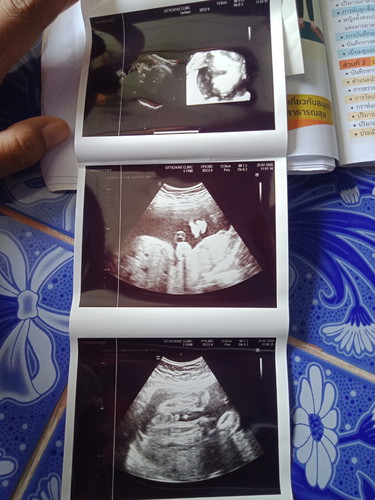

26สัปดาห์

น้ำหนักเท่าไหร่กันบ้างคะบ้านนี้. 1,038

บ้านนี้ท้องสองตอน26วีค พึ่ง860กรัมเองค่ะ หมอนัดอีกที29วีค ลุ้นมากจะถึงโลมั้ย เพราะคนแรกผ่า39+5วีค 2290กรัมเองค่ะ

ของเราตอน 27wekk น้อง1080 กก.จ้า

บ้านนี้หนัก1041 ค่ะ

25 สัปดาห์ 1,000 กรัมจ้า

31+3. น้ำหนัก1866ค่ะ

28วีคน้ำหนัก1440ค่ะ